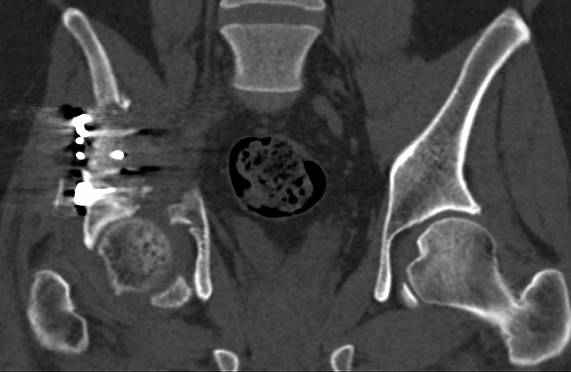

высылаю дополнительно сканы.

Судя по представленным реконструкциям (не очень хорошего качества - много наводок)

мы имеем дело с полупоперечным переломом у которого отломался задний край или его отломали, превратив перелом в полный двухколонный.

По отдельным срезам и тем более по реконструкции трудно судить о сращении крыла и задней колонны с осевым скелетом.

В большинстве случаев при двухколонных переломах

в итоге получается прочный бублик с дыркой. При эндопротезировании в дырку помещается головка, а чашка должна неплохо заклиниться в бублике.

Главное, чтобы бублик не был разорван, что не очень понятно на представленных снимках.

Все выступающие коллеги высказались насчет необходимости стандартных снимков по Judet, потому что для определения тактики лечения переломов вертлужной впадины 3Д снимки малоинформативны.

Из того минимума, что представлено, мне кажется, мы имеем дело с двухколонным переломом вертлужной впадины. Обычно медиальный (центральный) "вывих" головки встречаются в сложных двухколонных переломах со смещением.

Дополнительные сканы